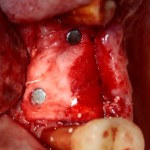

В этом случае остеопластика делается отдельной процедурой. Ее принципы точно те же, но уже без импланта. Например:

Имплантировать в таких условиях — заведомо обрекать себя на хреновый, с точки зрения эстетики и функциональности, результат. Поэтому первым этапом проводим остеопластику. Объем небольшой, использовать в таких объемах костный блок не очень рационально. Воспользуемся аутокостной стружкой и мембраной.

Сначала фиксируется BioGide. Это легко:

Затем укладывается и конфигурируется аутокостная стружка:

Если после этого BioGide намочить физраствором, им легко укрыть получившийся объем:

Для надежности можно зафиксировать пинами:

Ну и, швы: